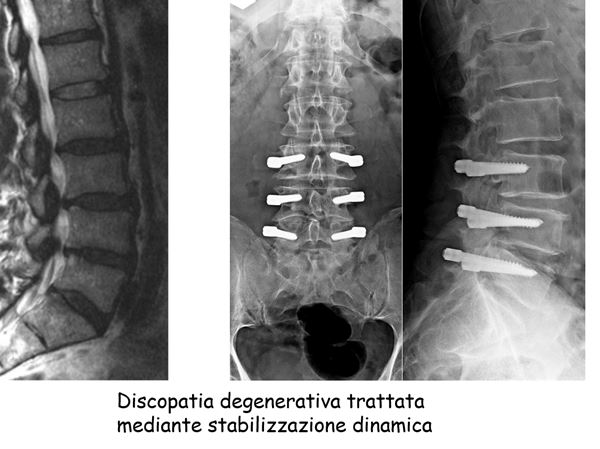

discopatia degenerativa